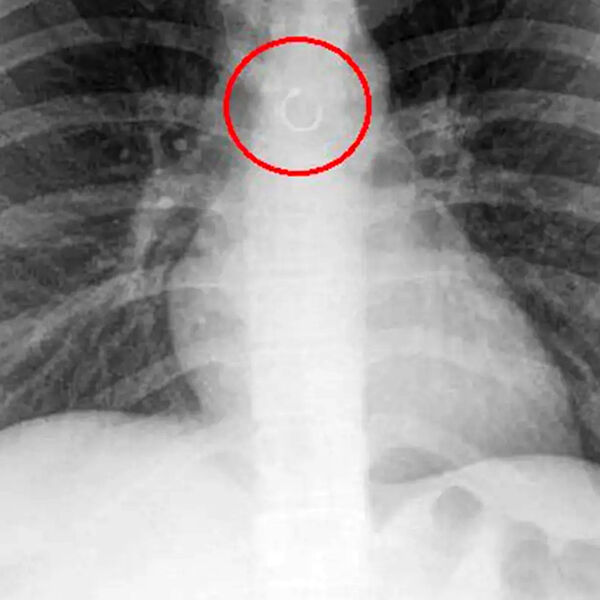

Женщина обнаружила, что потерянное кольцо в носу попало в ее легкие

В Мексике женщина обнаружила, что потерянное кольцо в носу попало в ее легкие, пишет Fox News.

Во время обследования выяснилось, что украшение из пирсинга в носу каким-то образом оказалось глубоко в дыхательных путях девушки и застряло в легких. Металлический элемент находился всего в полумиллиметре от аорты, что могло привести к опасным последствиям, добавили медики.